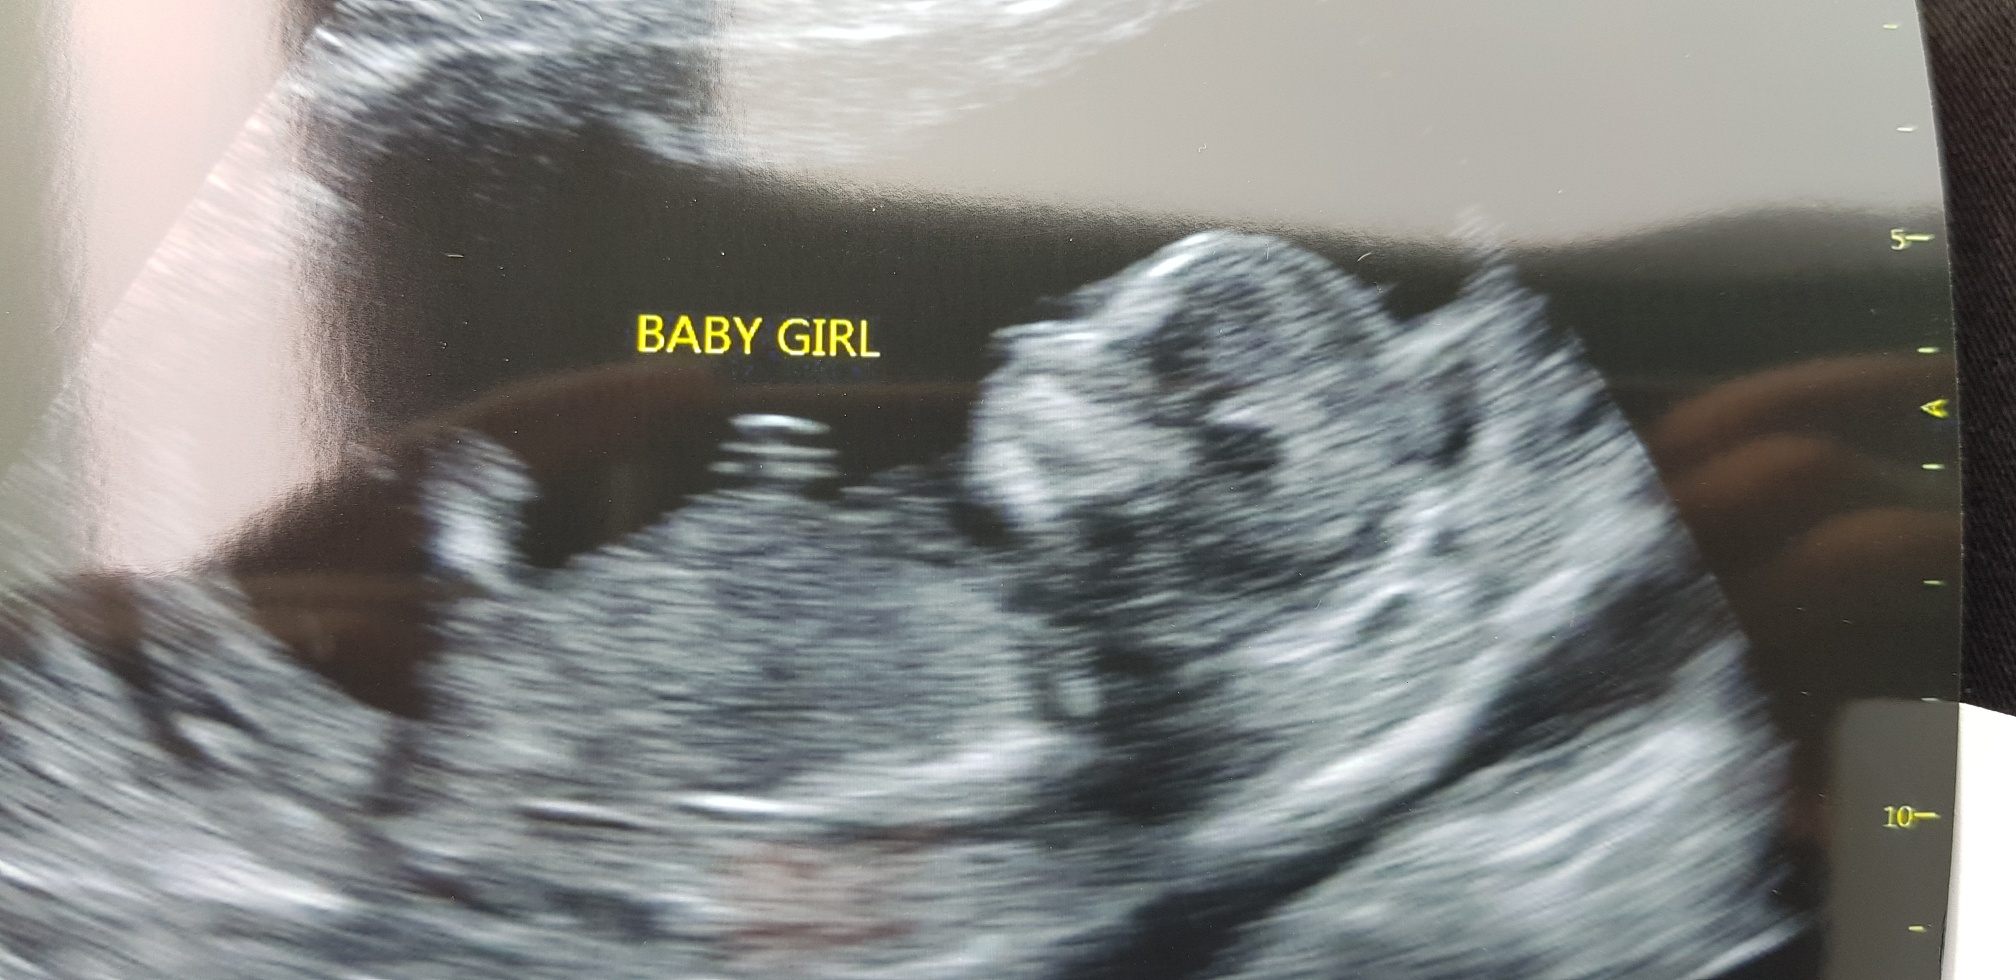

Hi everyone, bub would not stay still for more than 3 seconds so we couldn't get a clear image other than this one are there any gender clues?

I'm no expert at all but I cannot see a clear nub in this... looks very busy on that area and bub almost looks to be turning. Again I'm no expert so I may be totally wrong. Didn't want to view and not say anything though...

**If** the nub is visible I'm still indecisive... I'm 50/50 on this sorry, as there may be a flat line but not sure if it's the nub and not sure if there's stacking [emoji85] and honestly I don't even think the nub is visible....

Sorry I’d say the same, looks like cheeky bub is turning so image isn’t a real profile as needed for nub guesses. Will you get a 20w scan? Fx for you this is your boy! So many successful blue sways hope you get yours too ^^

Yes bub was turning again as she was trying to take the image it did not stay still i think im in for a real active bubba lol. I have another scan booked for this saturday i will be 14w2d i will try to get a better shot this time and update. Thanks for your good wishes but i feel like there has to be some opposites against the successful blue sways and feel like thats me silly i know to be thinking like this so early.

This was confirmed girl at 14 week scan, it will be our 3rd girl we swayed blue but theres only so much you can control i guess.. we had an early gender scan and the tech checked from 3 angles and its all girl. My phone doesn't allow me to upload photos to this site for some reason so i will have to do it from my laptop which wont be untill late tonight.

Updated photos at 14w1d can this really turn into a boy lolAttachment 41410Attachment 41411

It’s happened before but yes, it def looks girly..though at 14w, a potty shot is not 100% either, without wanting to give you hope IYKWIM? :)

BUT I do want to reiterate what someone said above - potty shots are not reliable that early and that is not a good nub shot for me anyway. It is my very great hope the tech is wrong, but of course guard your heart and still prepare for a girl for now.